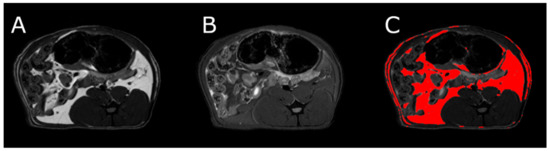

3.5. Body Composition

MRI measurements showed a significant reduction in the adipose tissue volume of ABA rats compared with controls (Figure 5). The mean visceral body fat reduction in the ABA rats reached 58.9% on day 6 of the experiment (Figure 6).

Figure 5.

MRI scan of female healthy rat, the cross section of the abdomen at L4 level. (A) RARE image without fat suppression; (B) fsupRARE image with fat suppression; (C) segmentation result—adipose tissue marked in red.

Figure 6.

MRI scan of female ABA rat, the cross section of the abdomen at L4 level. (A) RARE image without fat suppression; (B) fsupRARE image with fat suppression; (C) segmentation result—adipose tissue marked in red.